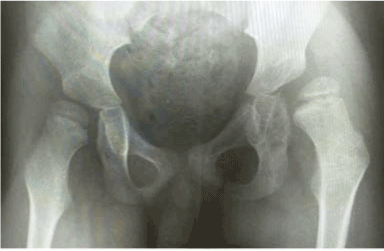

Radiographic assessment was performed with use of Migration Percentage (MP) of Reimers [16], Migration Percentage Difference (MPD) and Pelvic Obliquity Angle (POA). The MP describe the subluxation of the femoral head out of the acetabulum relative to the width of femoral head [17]. The MPD is the difference between the MP of one hip and the MP of the other hip in the same patient. We believe that high percent of the MPD is relative to high degree of pelvic obliquity. The POA is an angle between the line of the lowest edge of both ischium and horizontal line. It imply degree of pelvic obliquity as well (Figures 1-3).

Figure 1. The migration percentage difference (MPD), the right hip MP=58% and the left hip MP=24%.the MPD =58%-24%=34%. High percent of MPD imply high degree of pelvic obliquity angle.

Figure 2. The pelvic obliquity angle (POA) consist of the 1st line(horizontal line) cross the second line(a line drawn from the lowest edge of both ischium).In this figure, POA is equal to 6.8 degree.The x-ray film is belong to a 10 years-old girl with GMFCS level III. She walked with a walker frame in pattern of scissor gait and pelvic obliquity before operation. The right hip migrated 58% but the left hip migrated just 24% and the pelvic obliquity angle about 6.8 degree. The left hip had adduction, internal rotation contracture and the proximal femur showed coxa valga.